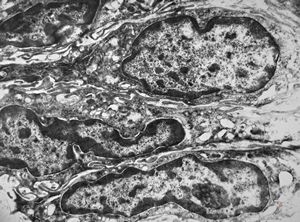

F,41y. | synovial metaplasia - capsule of implantate